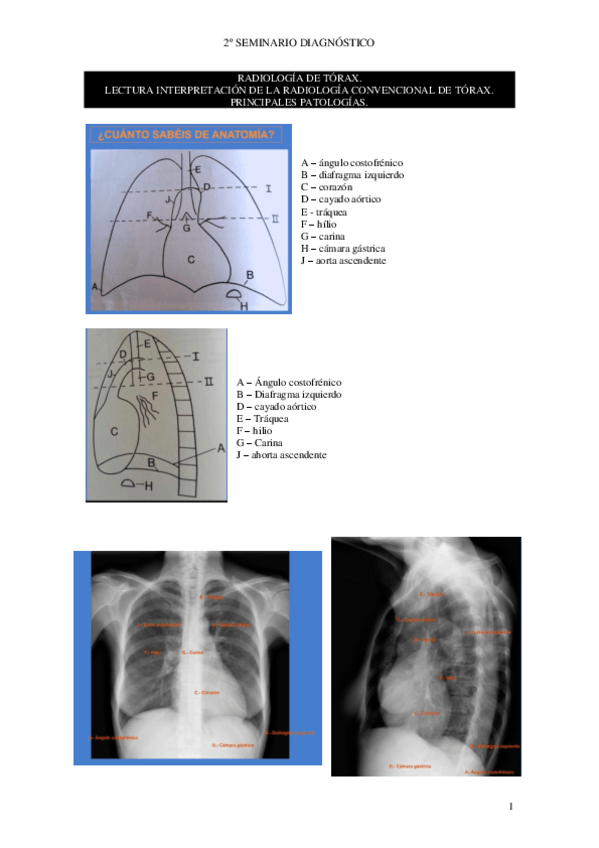

Practica-1-Tecnica-Anatomia-Torax.pdf